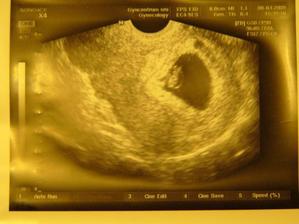

Nas maly prcek